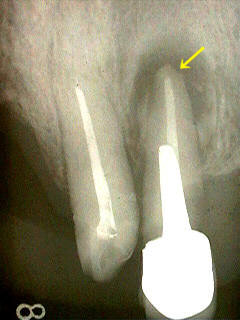

また、平面レントゲンやCT画像では完全な根充と見なされる症例でも根尖部に病巣のある症例がしばしば見られます。(参照:Phot3,Phot4) これらの画像から判明するように複雑な根管形態に完全な根充を行うことは神業といえます。

Photo-2.歯根のう胞(Radicular cyst)